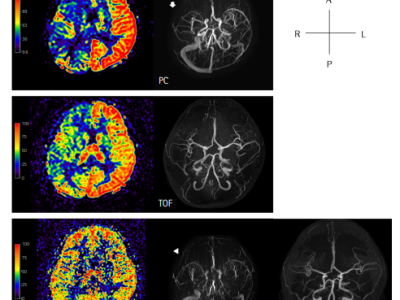

Serial Perfusion and Vascular Changes after a Prolonged Seizure

-